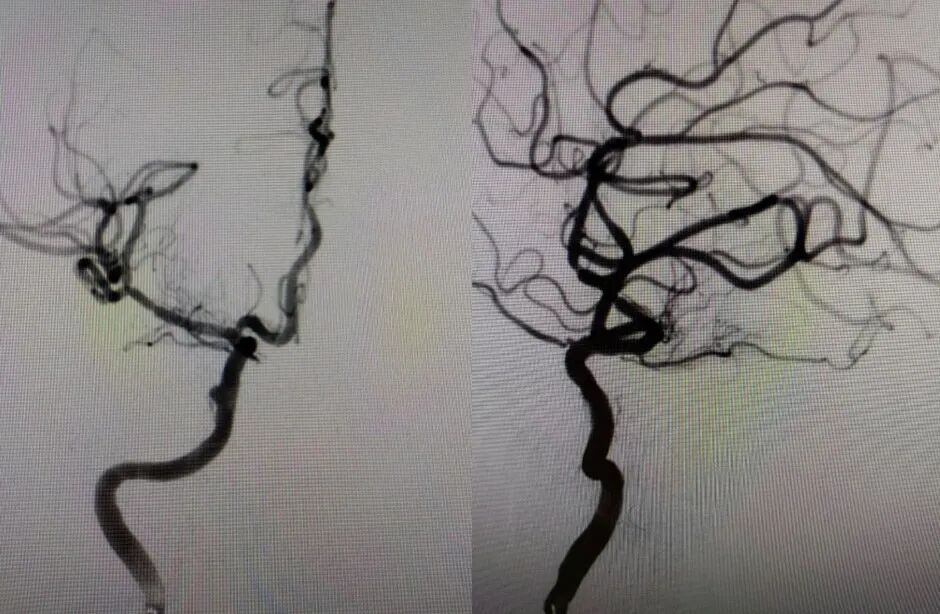

治疗中影像

Guiding到位,导丝通过病变。

导丝怎么扩【载药时代 球扩天下】NOVA DES®颅内药物洗脱支架在大脑中动脉重度狭窄的应用二例!_https://www.jmylbn.com_新闻资讯_第24张

球囊通过病变。

导丝怎么扩【载药时代 球扩天下】NOVA DES®颅内药物洗脱支架在大脑中动脉重度狭窄的应用二例!_https://www.jmylbn.com_新闻资讯_第25张

球囊扩张过程。

导丝怎么扩【载药时代 球扩天下】NOVA DES®颅内药物洗脱支架在大脑中动脉重度狭窄的应用二例!_https://www.jmylbn.com_新闻资讯_第26张

扩张后造影。

导丝怎么扩【载药时代 球扩天下】NOVA DES®颅内药物洗脱支架在大脑中动脉重度狭窄的应用二例!_https://www.jmylbn.com_新闻资讯_第27张

支架通过病变。

导丝怎么扩【载药时代 球扩天下】NOVA DES®颅内药物洗脱支架在大脑中动脉重度狭窄的应用二例!_https://www.jmylbn.com_新闻资讯_第28张

支架释放。

导丝怎么扩【载药时代 球扩天下】NOVA DES®颅内药物洗脱支架在大脑中动脉重度狭窄的应用二例!_https://www.jmylbn.com_新闻资讯_第29张

术后影像及检查

术后正位造影。

导丝怎么扩【载药时代 球扩天下】NOVA DES®颅内药物洗脱支架在大脑中动脉重度狭窄的应用二例!_https://www.jmylbn.com_新闻资讯_第30张

术后侧位造影

导丝怎么扩【载药时代 球扩天下】NOVA DES®颅内药物洗脱支架在大脑中动脉重度狭窄的应用二例!_https://www.jmylbn.com_新闻资讯_第31张